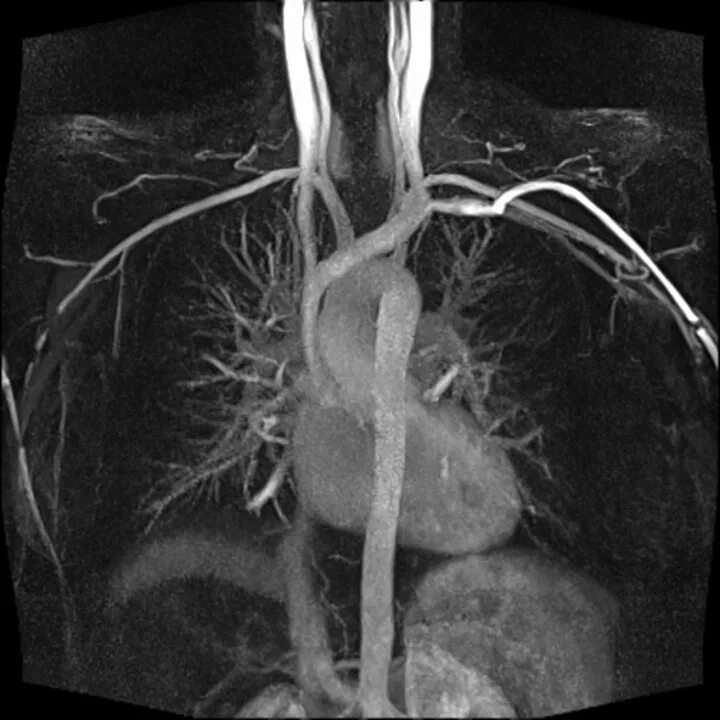

Мскт аортография